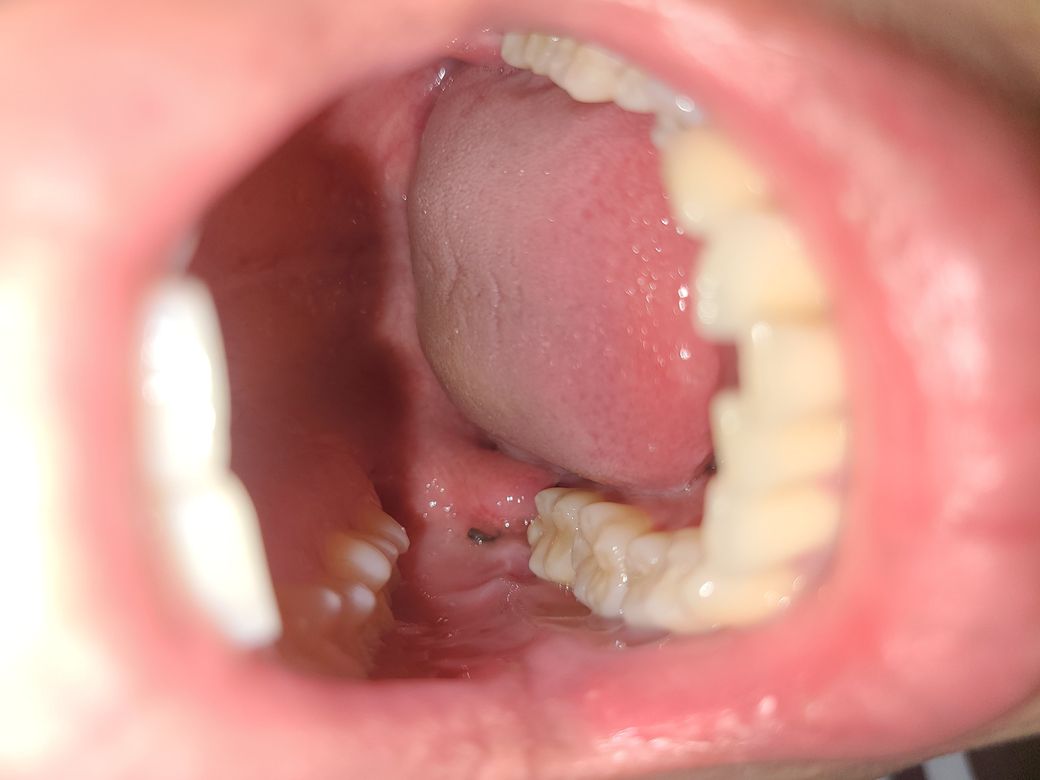

사랑니 발치 6일째인데 빨대사용 가능한가요?(사진첨부)

오늘로 사랑니발치 6일째인데 빨대사용가능한가요? 그리고........참지못해서 오늘 흡연을 했는데 발치부위가 조금 따끔거립니다 괜찮은건가요? 혹시 몰라 사진을 첨부 했습니다!

발치를 한부위에 약간의 부종이 보입니다.

발치 6일째이면 잘 아물고 있습니다. 실밥을 푸셨는지 봉합하지 확실하지 않지만 실밥도 안 보입니다.

현재 사진으로서는 회복이 정상적으로 진행되고 있는 것으로 보여집니다.